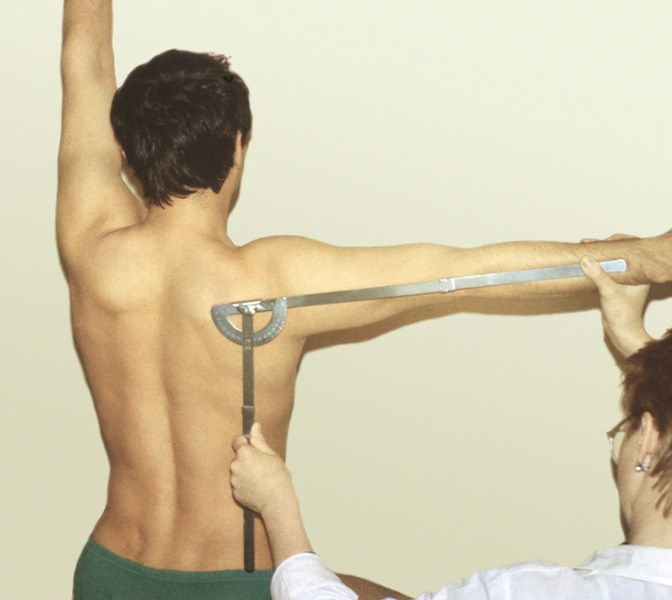

Диаграммы и схемы движения в суставах человека